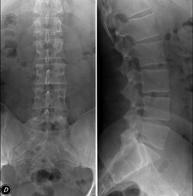

Tècnica que usa els raigs X a través de la qual s'obtenen imatges de la columna dorsal per al seu estudi. Indicacions: traumatisme, mal d'esquena. - RX Columna lumbar

Tècnica que usa els raigs X a través de la qual s'obtenen imatges de la columna lumbar per al seu estudi. Indicacions: ciàtica, traumatisme, dolor lumbar. - RX Sacre-còccix